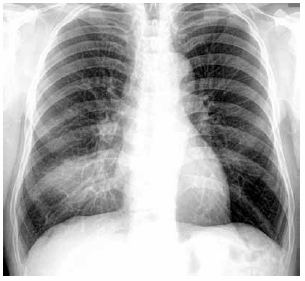

Homem de 51 anos de idade, em tratamento quimioterápico para câncer de cólon, apresenta quadro de mal-estar, sudorese, dispneia e tosse seca há 3 dias. O último ciclo da quimioterapia foi realizado há 10 dias. PA: 91 x 44 mmHg, FC: 114 bpm, FR: 28 ipm, SatO2: 89% e T: 38,3 ºC; tórax e abdome: NDN. Leucograma: 195/mm3. A radiografia de tórax realizada é apresentada a seguir.